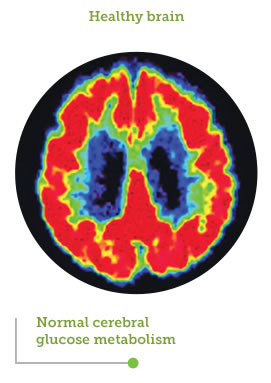

FDG-PET showing areas of cerebral glucose metabolism

Image source: Small GW, Ercoli LM, Silverman DHS, et al. Cerebral metabolic and cognitive decline in persons at genetic risk for Alzheimer’s disease. Proc Natl Acad Sci USA. 2000;97(11):6037-6042. Copyright 2013 National Academy of Sciences, U.S.A.

The brain’s capacity to utilize glucose as fuel is diminished by up to 25%, leaving a large portion of its energy needs unfulfilled1